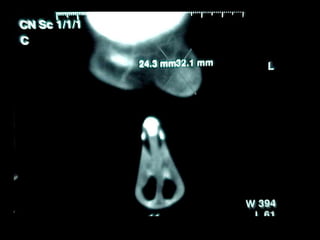

Eliminación de focos sépticos en bloque en paciente con osteitis

mandibular crónica

Osteitis

Imagen microscópica de osteitis, inicialmente existe una etapa de

osteoclastosis seguida por regeneración. No siempre el hueso

regenera en su totalidad y sigue el curso de cualquier inflamación

dejando un area de tejido fibroso que con el tiempo puede

calcificarse (hueso denso)

Manejo con antibióticos obligado

Revisión periódica